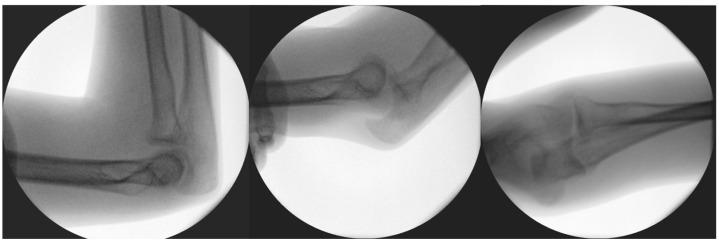

小儿冠状突骨折的手术治疗:两例报告

Surgical Management of Pediatric Coronoid Process Fractures: A Report of Two Cases.

Coronoid process fractures in the pediatric population are rare and often misdiagnosed, leading to chronic elbow instability. We aim to evaluate the surgical management of two adolescent cases of inveterate coronoid fractures using autologous bone grafting. Both patients, with a history of recurrent elbow dislocations, presented with pseudoarthrosis and were initially misdiagnosed due to minor or subtle fractures. Comprehensive imaging, including computed tomography (CT) and magnetic resonance imaging (MRI), confirmed the presence of significant coronoid defects. The surgical intervention involved employing autografts from the iliac wing to reconstruct the coronoid process, followed by fixation with screws. Both patients underwent postoperative rehabilitation via physiotherapy, resulting in full functional recovery. At their one-year follow-ups, both patients regained full elbow function, achieving range-of-motion measurements of 0-0-130° flexion-extension and 90-0-90° pronation-supination; no recurrence of instability was reported, with no complications at the yearly follow-ups. This approach demonstrates the efficacy of autograft reconstruction in restoring elbow stability, particularly in cases with substantial bone loss or pseudoarthrosis. Our study highlights the importance of advanced imaging and individualized treatment strategies, emphasizing that early surgical intervention can prevent long-term disability in pediatric patients with chronic coronoid fractures.

摘要

小儿冠状突骨折较为罕见,且常被误诊,从而导致慢性肘关节不稳定。我们旨在评估两例青少年陈旧性冠状突骨折采用自体骨移植的手术治疗方法。两名患者均有复发性肘关节脱位病史,表现为假关节形成,最初因骨折轻微或不明显而被误诊。包括计算机断层扫描(CT)和磁共振成像(MRI)在内的综合影像学检查证实存在明显的冠状突缺损。手术干预包括采用来自髂骨翼的自体骨移植来重建冠状突,随后用螺钉固定。两名患者术后均通过物理治疗进行康复,最终实现了功能完全恢复。在一年的随访中,两名患者均恢复了完全的肘关节功能,屈伸活动度达到0-0-130°,旋前旋后活动度达到90-0-90°;未报告不稳定复发情况,年度随访也未出现并发症。这种方法证明了自体骨移植重建在恢复肘关节稳定性方面的有效性,特别是在存在大量骨质流失或假关节形成的病例中。我们的研究强调了先进影像学检查和个体化治疗策略的重要性,强调早期手术干预可以预防慢性冠状突骨折小儿患者的长期残疾。